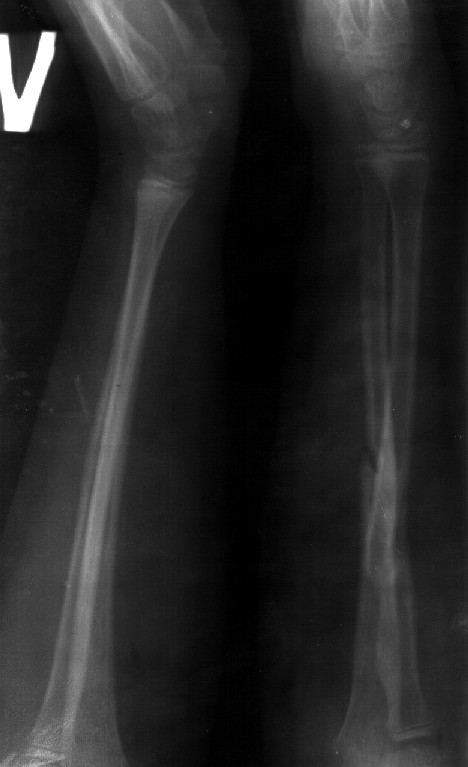

Re: Консолидированный перелом костей предплечья

Снимок один сделан с супинацией, второй - оба предплечья в одинаково нейтральном положении. то есть по этим снимкам объем ротационных движений не оценить. Снимко в двух проекциях лучше и делать в среднем положении между пронацией и супинацией, то есть обе проекции в однм и том же положении, когда линия, проходящая через шиловидные отростки, идет в плоскости головки. Прошу прощения за усложнение простых вещей.